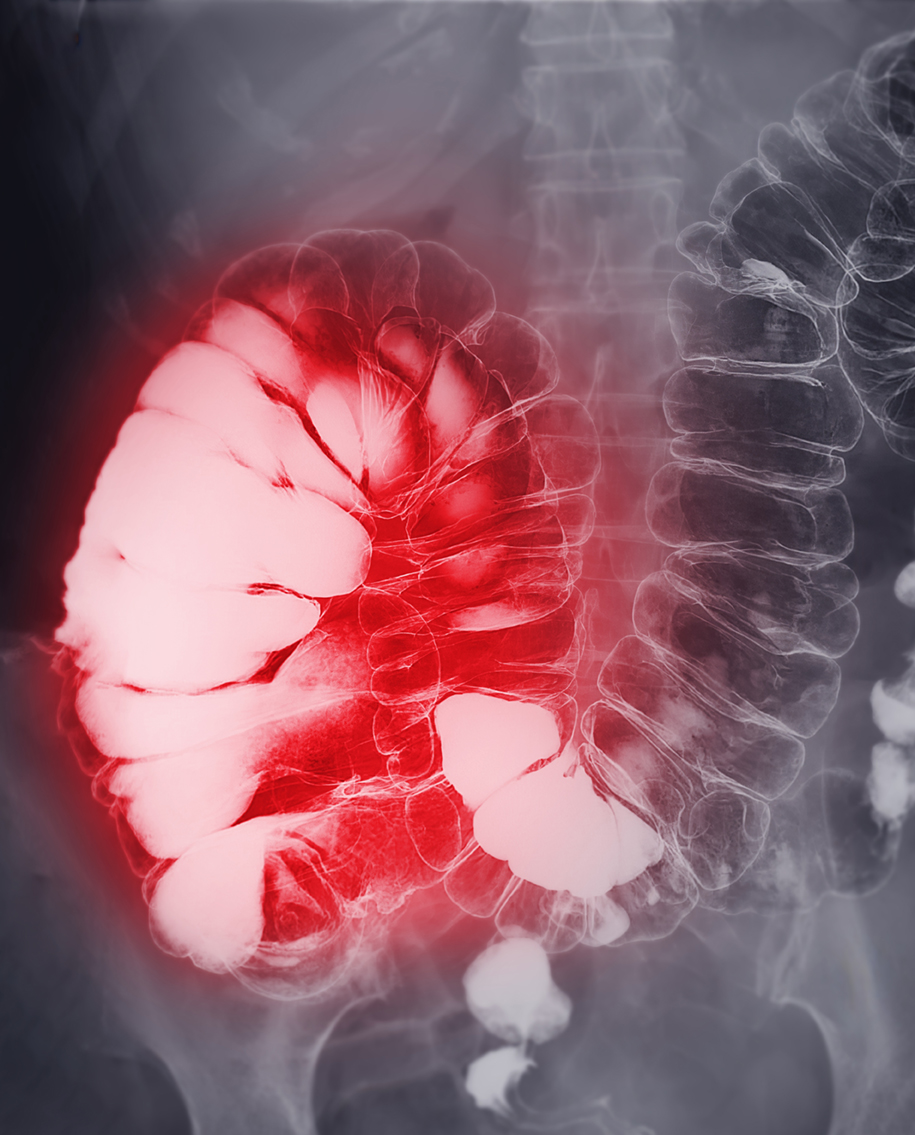

また、オーストラリアには、大腸がんではない人のライフスタイルや身体活動などのデータを比較した調査があります。

Barium enema or BE is image of large bowel after injection of barium contrast fill into colon under fluoroscopic control isolated on white background for diagnosis colon cancer.

画像:下部消化管造影またはBEは、結腸癌の診断のために白い背景にX線透視下で結腸に造影剤を注入した後の大腸の画像

その調査を分析した結果、10年以上デスクワークをおこなってきた人は、デスクワークに就いたことがない人と比較して、大腸がんのリスクが2倍であり、直腸がんのリスクは44%も高かったというのです。